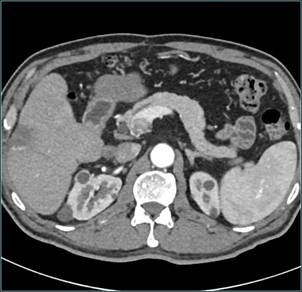

患者男,51岁,发现肝脏占位1周入院,入院后积极完善相关检查,CT提示患者肝脏巨大占位,门静脉受侵犯可能,已无法行外科根治性切除,经MDT讨论拟定行经桡动脉入路肝癌介入治疗+靶向治疗。患者介入手术后3月余肿瘤明显缩小,最后手术切除,获得肿瘤根治。

术前CT: